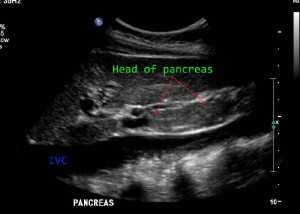

Поджелудочная железа лежит на задней брюшной стенке с головой в виде буквы С исходящей из двенадцатиперстной кишки. Тело и хвост простираются наклонно вверх влево, хвост поджелудочной железы лежит в селезеночно-ренальной связке рядом с селезенкой и верхним полюсом левой почки. Головка поджелудочной железы имеет крючковидный отросток, который распространяется позади нижней части верхней брыжеечной вены в начале воротной вены. Крючковидный отросток распространяется ниже основного тела поджелудочной железы, поэтому важно при ультразвуковом исследовании сканировать всю протяженность поджелудочной железы, иначе может быть пропущен рак крючковидного отростка.

Поджелудочная железа лежит в переднем параренальном пространстве. Головка лежит в изгибе петли двенадцатиперстной кишки с нижней полой веной и правыми почечными сосудами, лежащими сзади. Общий желчный проток получает главный проток поджелудочной железы, когда он проходит через головку поджелудочной железы, а затем дренируется во вторую часть двенадцатиперстной кишки в ампуле Фатера. Гастродуоденальная артерия может быть видна спереди в области поджелудочной железы и шейке. Головка поджелудочной железы - самая выпуклая часть железы, которая затем сужается в области шейки. Объединение верхних брыжеечных и селезеночных вен, образующих портальную вену сзади, отмечает анатомическое положение шейки поджелудочной железы. Привратник и гастродуоденальная артерия расположены спереди. Малая кривизна желудка лежит впереди тела поджелудочной железы, в то время как селезеночная вена проходит вдоль ее задней верхней поверхности. Хвост поджелудочной железы связан с селезенкой, левым надпочечником и верхним полюсом левой почки.

Определение положения поджелудочной железы. Головка поджелудочной железы

Именно в этой проекции располагается поджелудочная железа, которая анатомически состоит из трех отделов:

- Тело (ширина до 21-25 мм), имеющее центральное расположение относительно проекции позвоночного столба, и лежащее непосредственно под желудком (отсюда и название органа);

- Головка (до 32-35 мм), незначительно выступающая вправо относительно позвоночника и граничащая с 12-перстной кишкой;

- Хвост (до 30-35 мм), отходящий к левому подреберью и селезенке.

- Контуры железы должны быть ровными, четкими, с хорошей визуализацией как основных отделов органа, так и крючковидного отростка с перешейком.

- Вирсунгов проток должен хорошо визуализироваться, не будучи при этом расширенным.